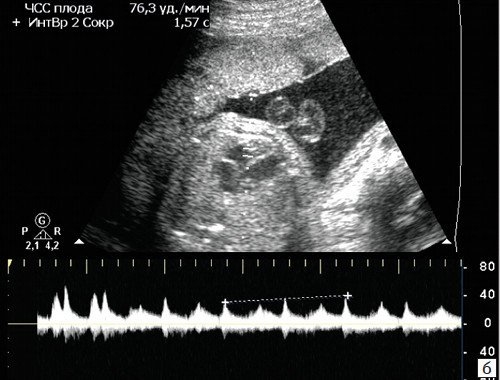

При предсердной бигеминии или тригеминии (преждевременных блокированных сокращениях предсердий) частота сокращений желудочков плода может снижаться до 60-100 уд/мин. При этом блокируется проведение к желудочкам каждого второго (бигеминия) либо каждого третьего (тригеминия) предсердного импульса (рис. 7-9).

а) Каждое третье сокращение предсердия (стрелка) возникает преждевременно и блокируется, не проводится к желудочку.

б) В результате формируется желудочковая брадисистолия 76 уд/мин.